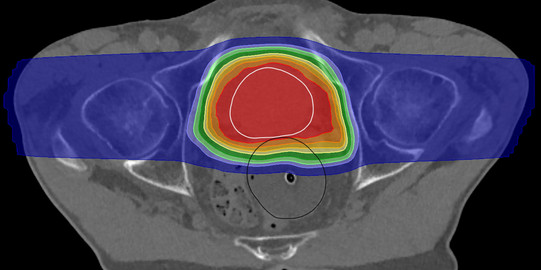

Medizin ist mehr und mehr auch angewandte Physik. Längst sind hochkomplexe und ausgefeilte Geräte weder aus Krankenhäusern noch aus Arztpraxen wegzudenken. Ultraschallsensoren zeigen Ablagerungen in Arterien, starke Magnetfelder in Tomographen machen Muskeln, Organe und Fett sichtbar. Nicht nur bei der Diagnose, auch bei der Behandlung geht es physikalisch zu: Laser schneiden genauer als Skalpelle, Beschleuniger zerstören Tumore mit hochenergetischer Strahlung und schonen gesundes Gewebe rundherum.

Um diese komplexe Technik zu entwickeln und anzuwenden, braucht es Expertinnen und Experten. Es braucht Medizinphysiker*innen. Mit ihrem physikalischen Wissen helfen sie, die Medizin besser, sicherer und damit auch menschlicher zu machen. Dabei schlagen sie eine Brücke zwischen den Disziplinen, aber auch zwischen Industrie und Krankenhaus. Medizinphysiker*innen entwickeln nicht nur die erforderlichen Technologien, sie sind es auch, die sie bei Patient*innen einsetzen. Das verlangt nicht nur fachliches Können, sondern auch Verantwortungsbewusstsein und Geschick im Umgang mit Menschen.